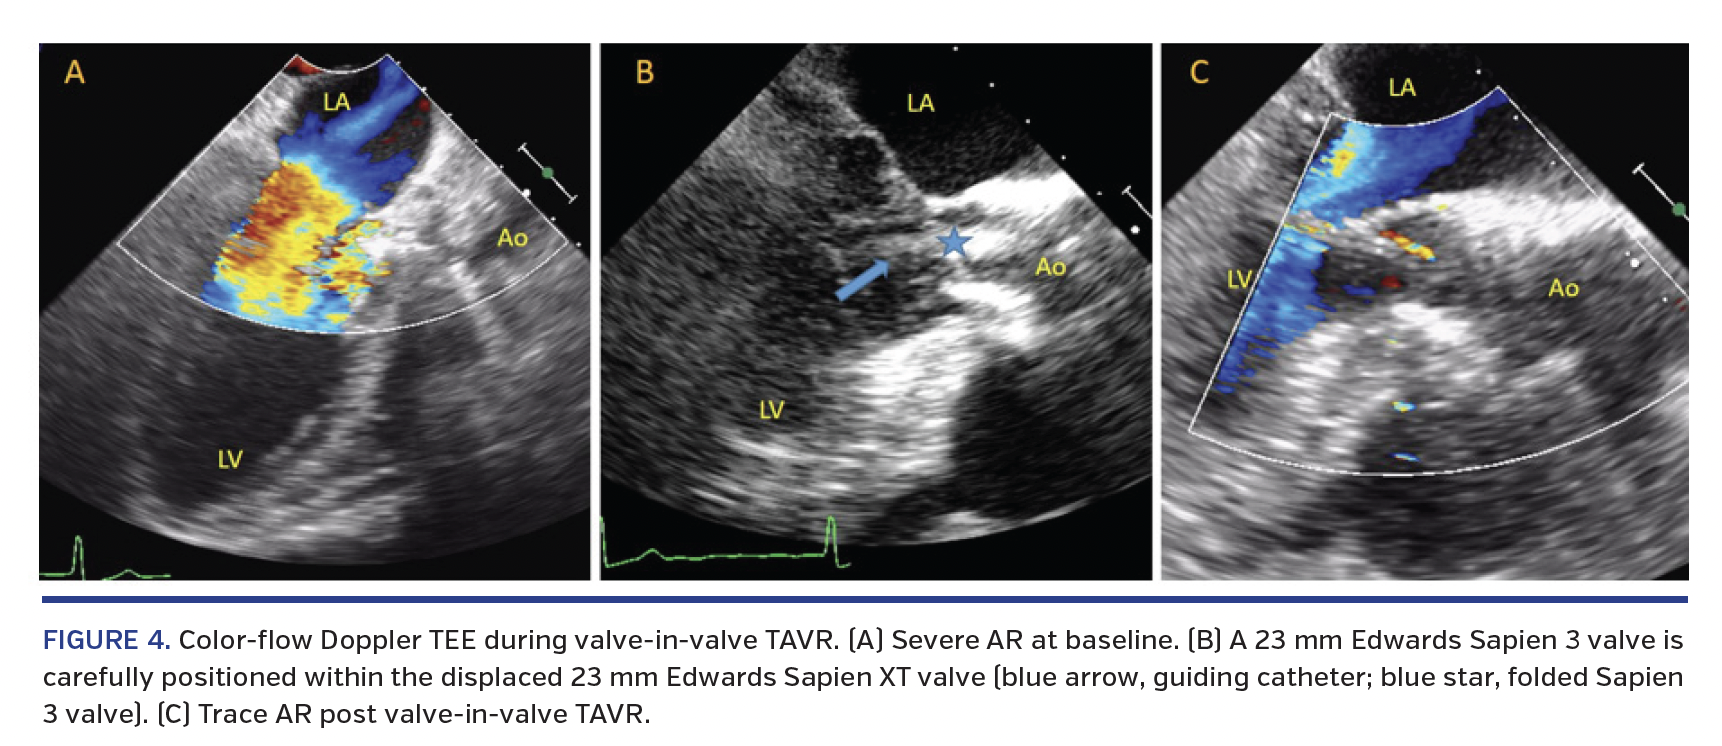

A 70-year-old woman was re-admitted to the emergency department with recalcitrant heart failure symptoms that had initially abated following initiation and optimization of diuretic therapy. Past medical history was significant for heart failure with preserved ejection fraction, chronic obstructive pulmonary disease, and aortic stenosis treated with transcatheter aortic valve replacement (TAVR) 3 years prior, with a 23 mm Edwards Sapien XT valve (Edwards Lifesciences). Physical exam was remarkable for bibasilar crackles, 3/6 pansystolic murmur heard best at the apex with radiation to the axilla, and 3/6 harsh, diastolic decrescendo murmur heard best at the lower left sternal border. Transthoracic echocardiogram showed severe mitral regurgitation (MR) with an eccentric posterolateral jet and moderate aortic regurgitation (AR) with peak velocity of 3.8 m/sec, mean gradient of 32 mm Hg, and valve area of 1.2 cm2. Three-dimensional transesophageal echocardiogram (3D-TEE) demonstrated two MR jets (Figure 1) and severe AR. There was a migrated aortic prosthesis below the native aortic valve leaflets (Figure 2). In addition, the displaced prosthesis may have disrupted the mitral subvalvular apparatus, leading to a flail P1 scallop. These findings were confirmed by inversion mode volume-rendered and multiplanar gated computed tomographic (CT) reconstruction (Figure 2E; Videos 1 and 2). A valve-in-valve TAVR was planned. Intraprocedural cone-beam CT imaging and aortic root angiogram showed the “slipped” Sapien XT valve (in comparison with the aortic root angiogram from 3 years ago) with severe AR, respectively (Figure 3). There was complete resolution of severe AR following valve-in-valve TAVR with a 23 mm Edwards Sapien 3 valve (Figure 4; Videos 3-5).